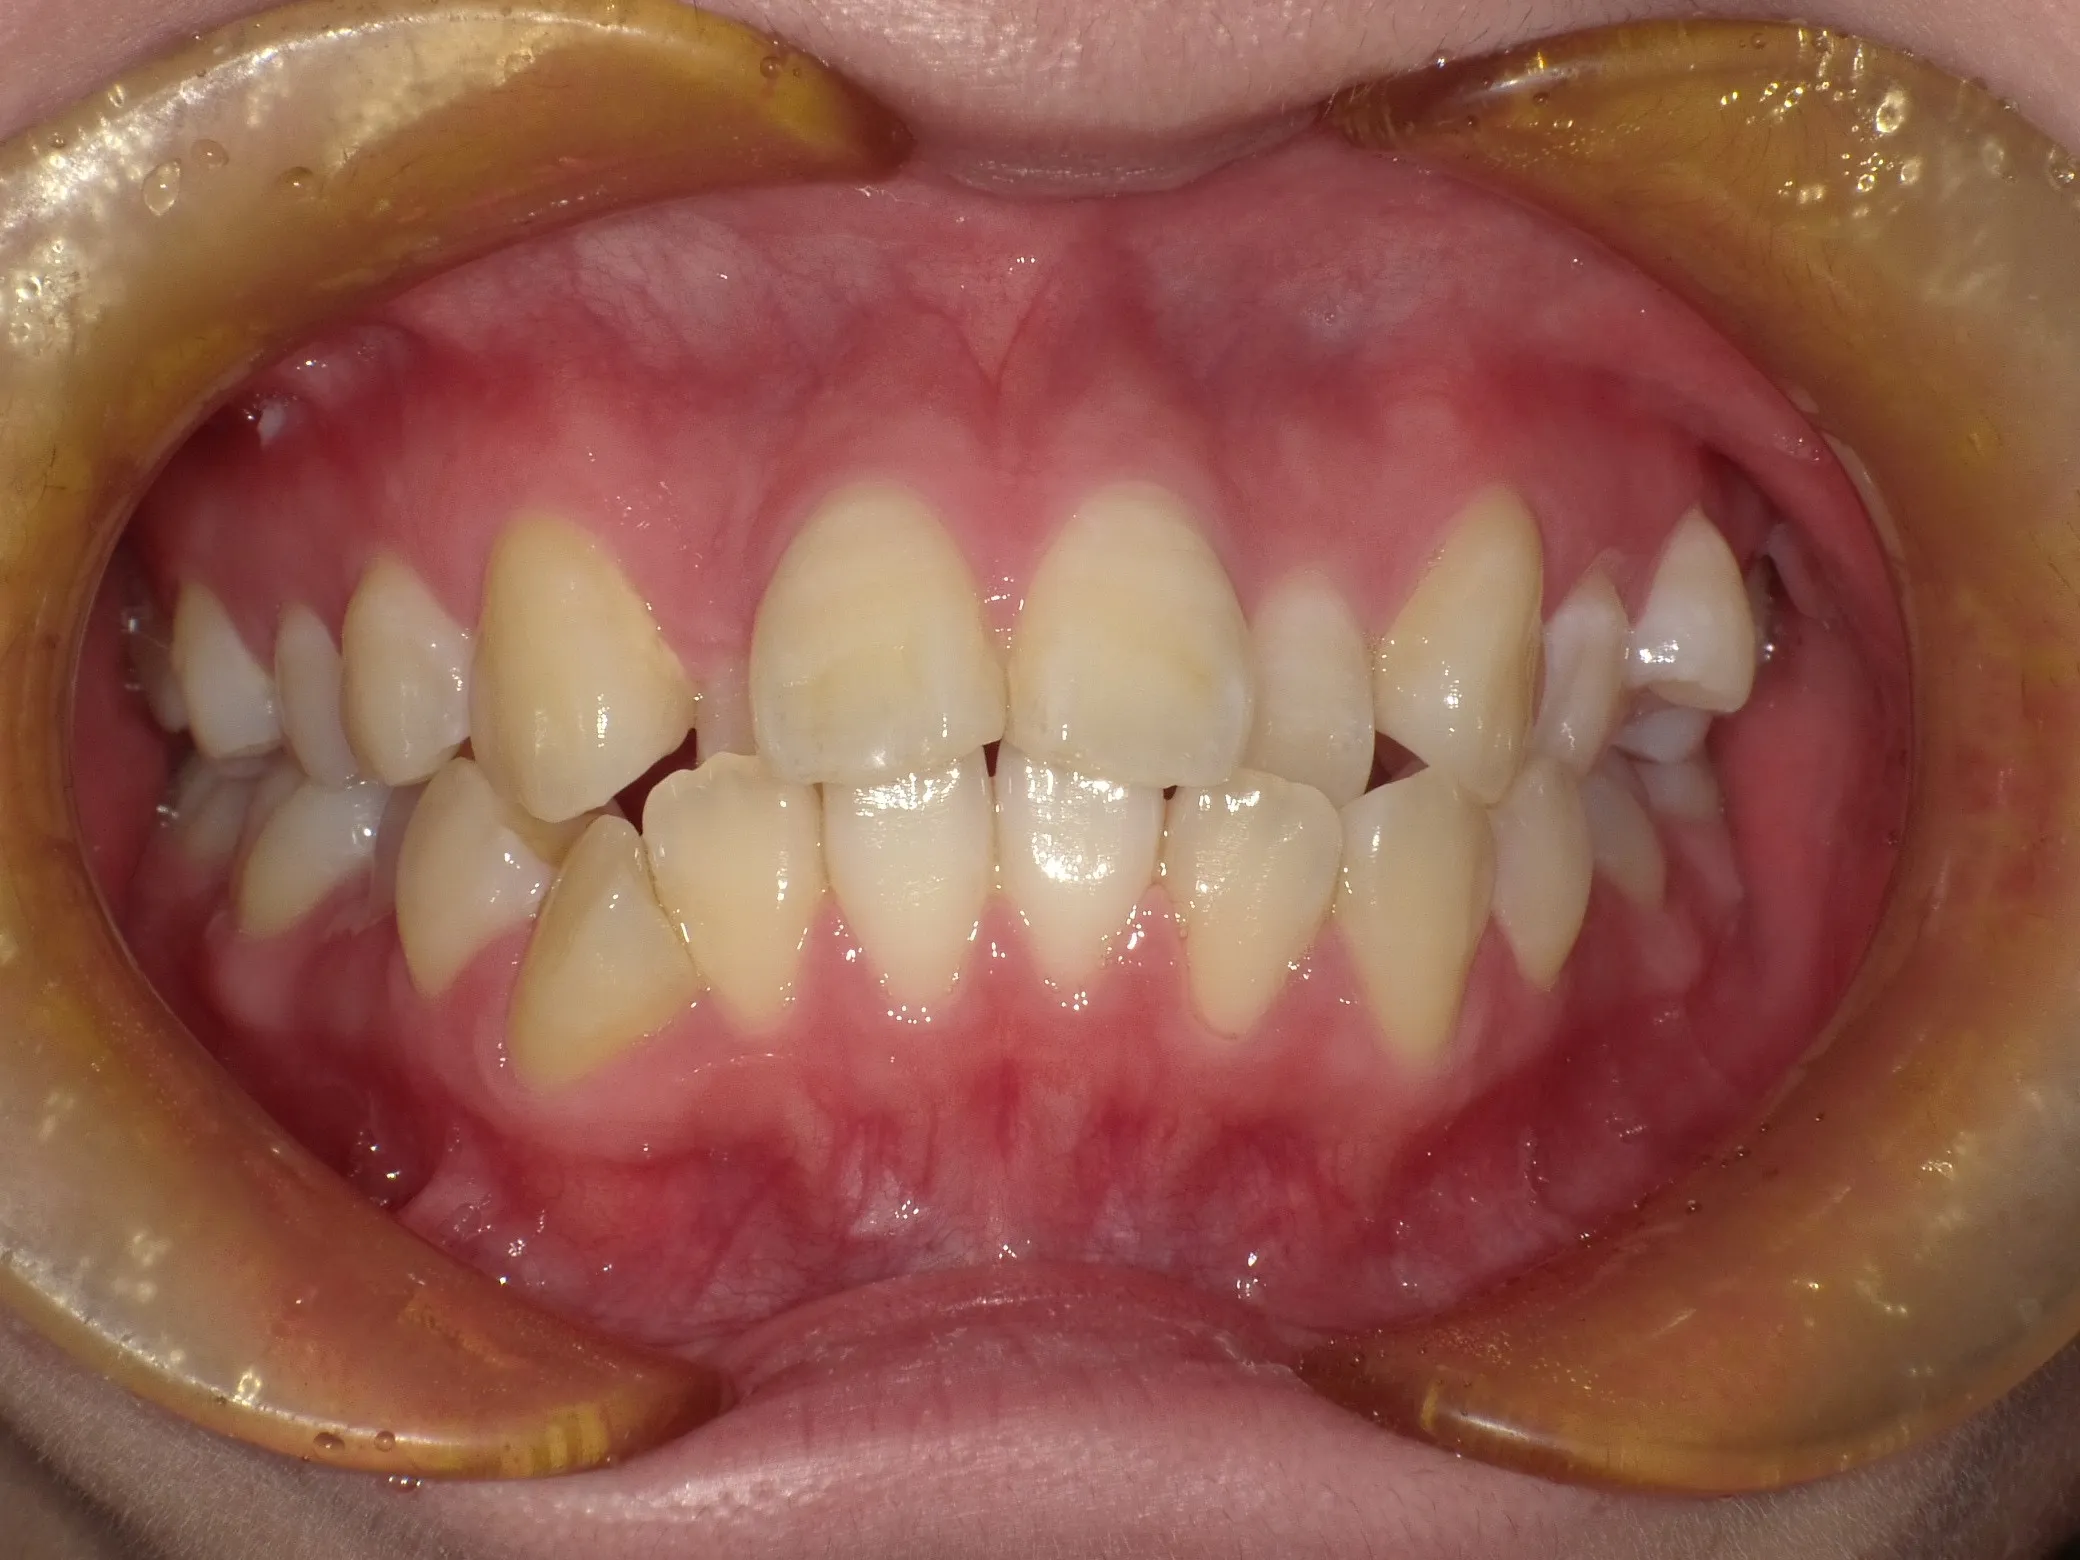

症例①

症例1_治療前 症例1_治療後

年齢(年代) 26才(当時)

治療方法 ホワイトブラケット

治療期間 3年

治療総額 825,000円

特記事項 抜歯あり